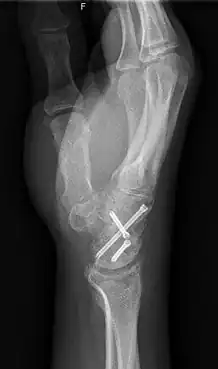

Arthrodesis is the surgical immobilization of bones within a joint to promote fusion of the joint.[5] Arthrodesis is performed most commonly on joints of the feet, hands, and spine.[6][7][8] Arthrodesis can relieve pain from arthritis and fractures.[9] This is accomplished through the use of orthobiologics such as allografts and autografts.[10] Allografts are done by creating bone grafts from a donor bone bank, whereas autografts are bone grafts from other bones in a patient's body.[10] Patient-reported outcomes following this procedure are typically positive in terms of long-term pain relief; however, the procedure also results in decreased range of motion.[11]

In the actual procedure, the bone affected by the tumor, as well as a small part of the healthy femur and occasionally tibia bone, is removed.[30] The ankle joint is then turned 180 degrees and is reattached to the thigh.[30] They are held together by plates and screws until they have healed naturally. The surgery can take anywhere from 6–10 hours, with a day or two in intensive care.[26] The leg is kept in a cast for 6–12 weeks. After the leg has sufficiently healed, the leg can be fitted for a prosthetic.[29]